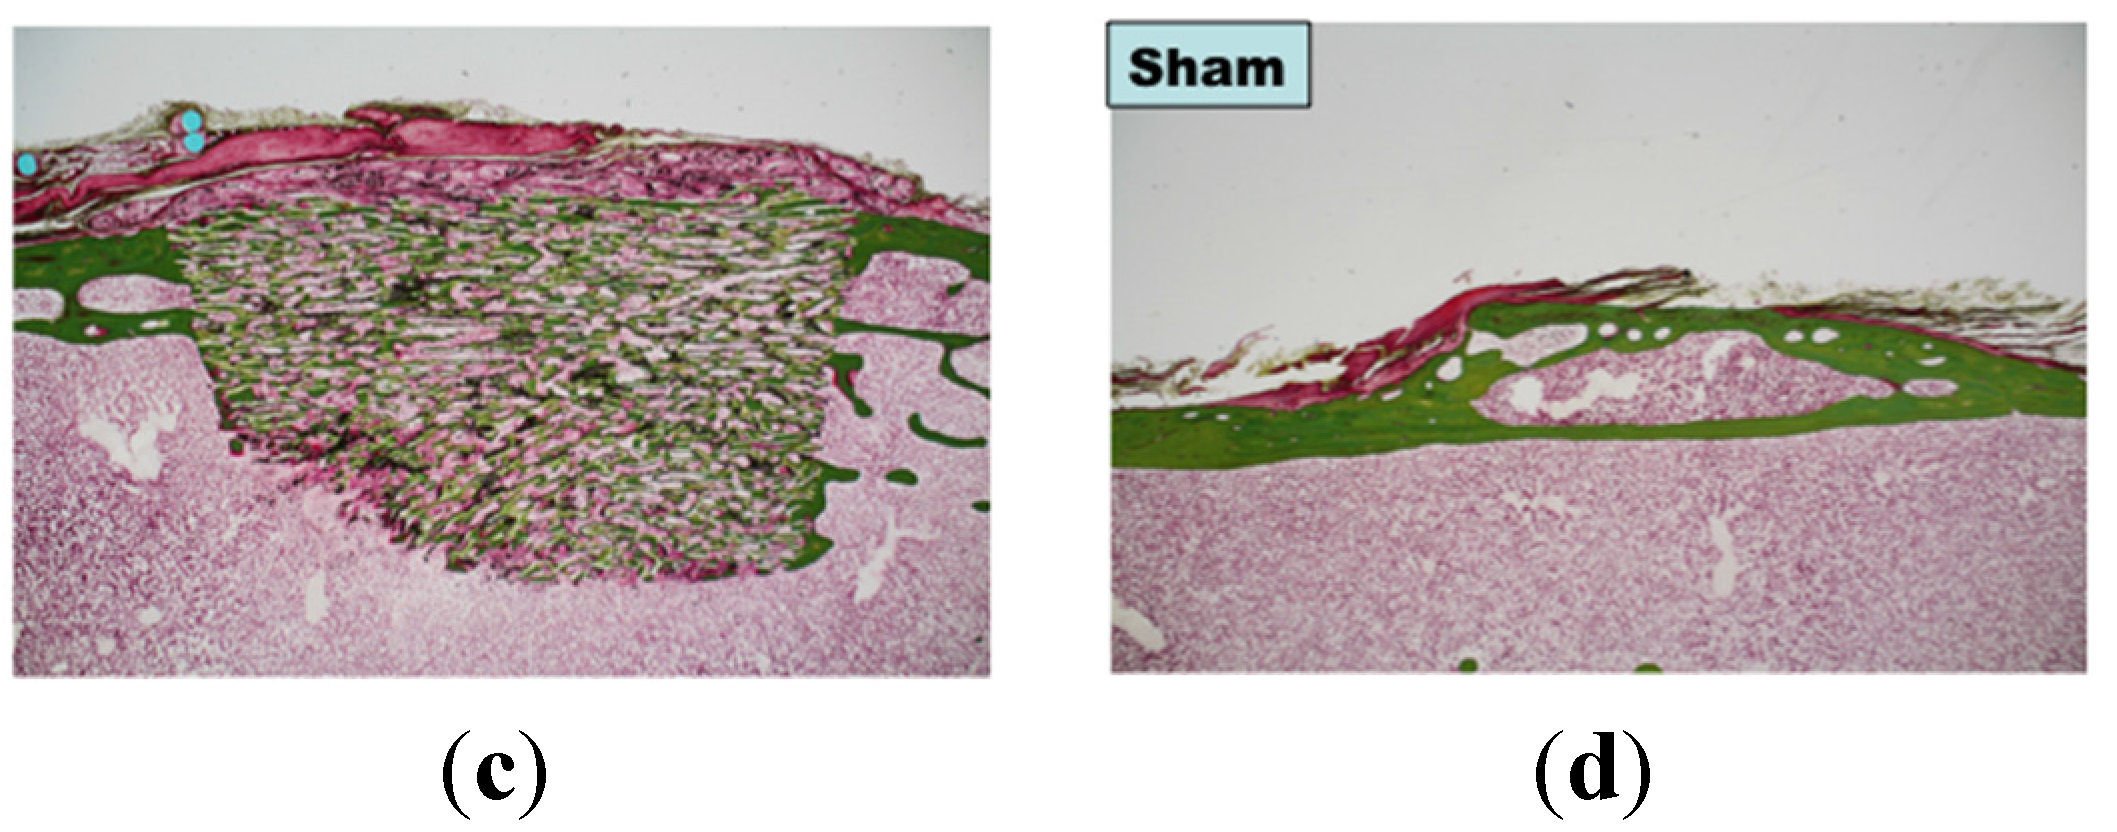

2. Results and Discussion

3.3. Bone Formation in Cortical and Medullary Bone Regions